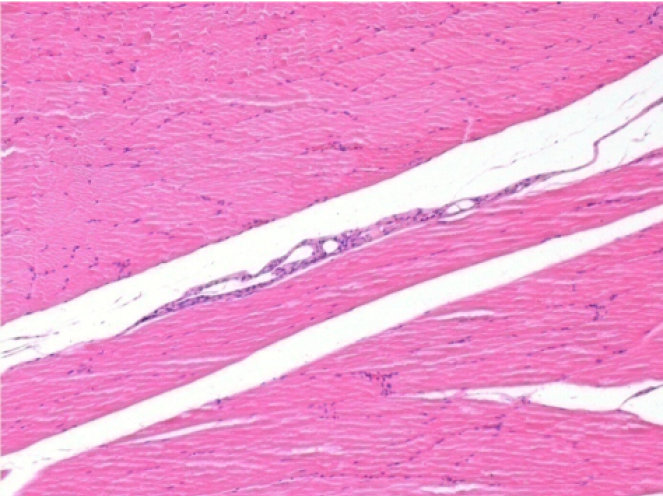

Yorum: Salin solüsyonu enjeksiyonundan sonra beyan edilecek bir şey yok

ol: Pretibial-Tedavi yok